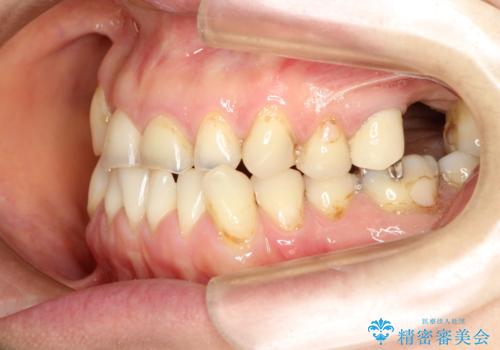

反対咬合や欠損を治療したい インビザライン矯正とオールセラミックブリッジ

- 虫歯治療がうまく進まないとのことで来院された患者様です。

虫歯治療や欠損補綴治療も必要でしたが、前歯が反対咬合であったので、セラミッククラウンやブリッジによる治療と並行して矯正治療を提案しました。